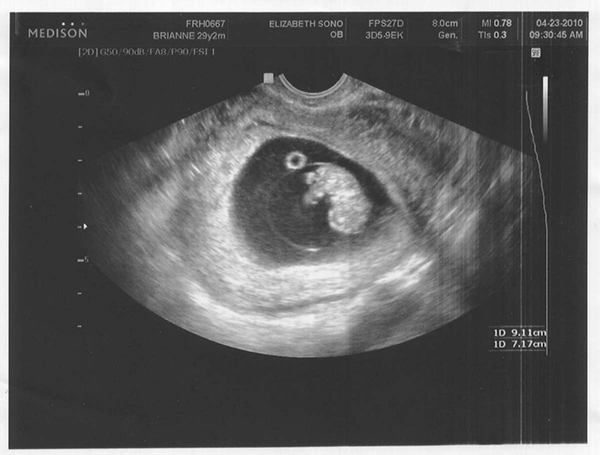

На маленьком сроке размеры плода не позволяют почувствовать его движения

1. Размеры ребенка. На 8 неделе он слишком маленький, чтобы маме были заметны его движения.

2. Околоплодная жидкость. Она занимает большую часть пространства на этом сроке, и мешает малышу достать до стенок брюшной полости.